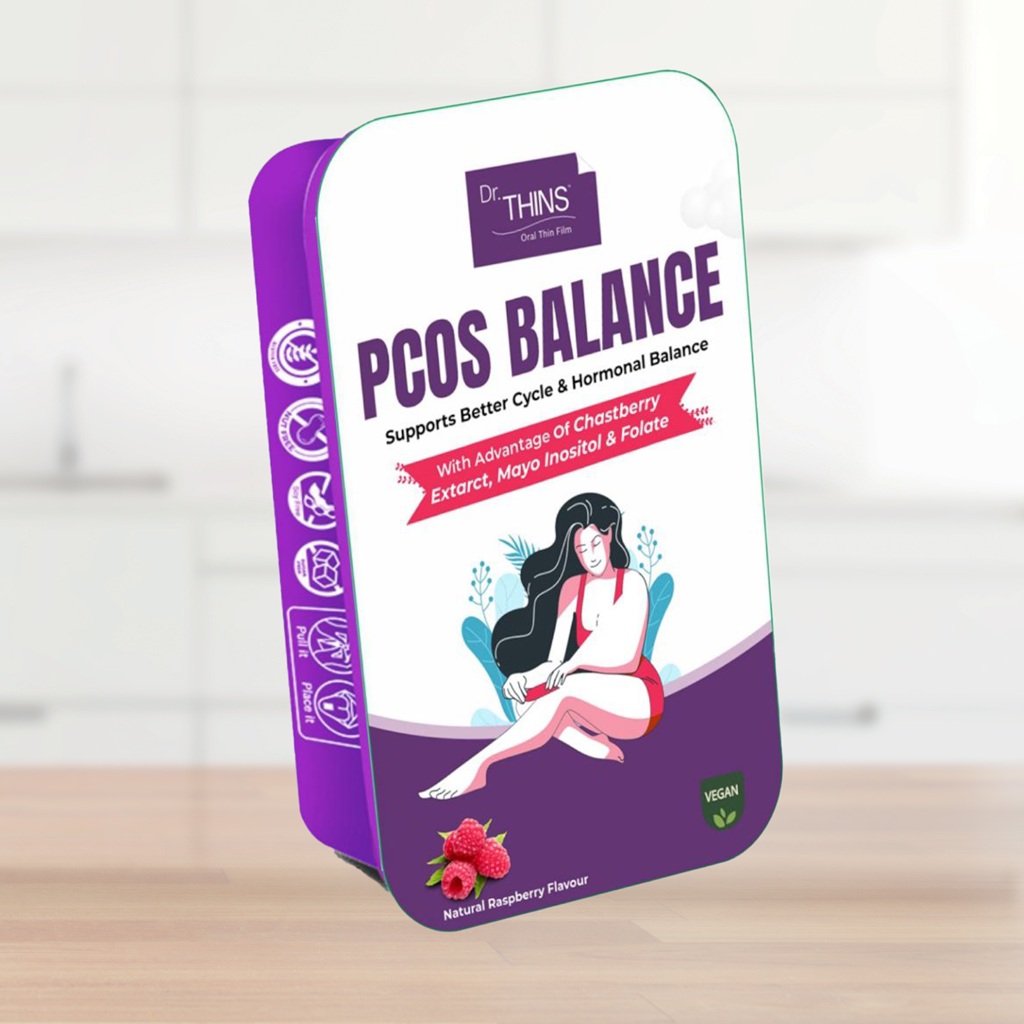

Dr. Thins Products

Vitamins and Dietary Supplements

Wellness Products

Wellness Products